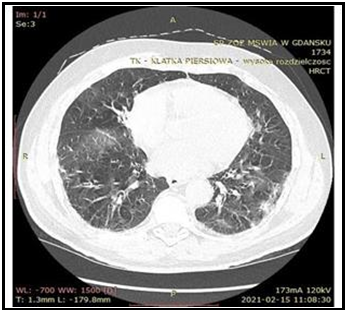

Isolated pauci-immune pulmonary capillaritis associated with an extensive bilateral hemothorax and pleuro-pericarditis